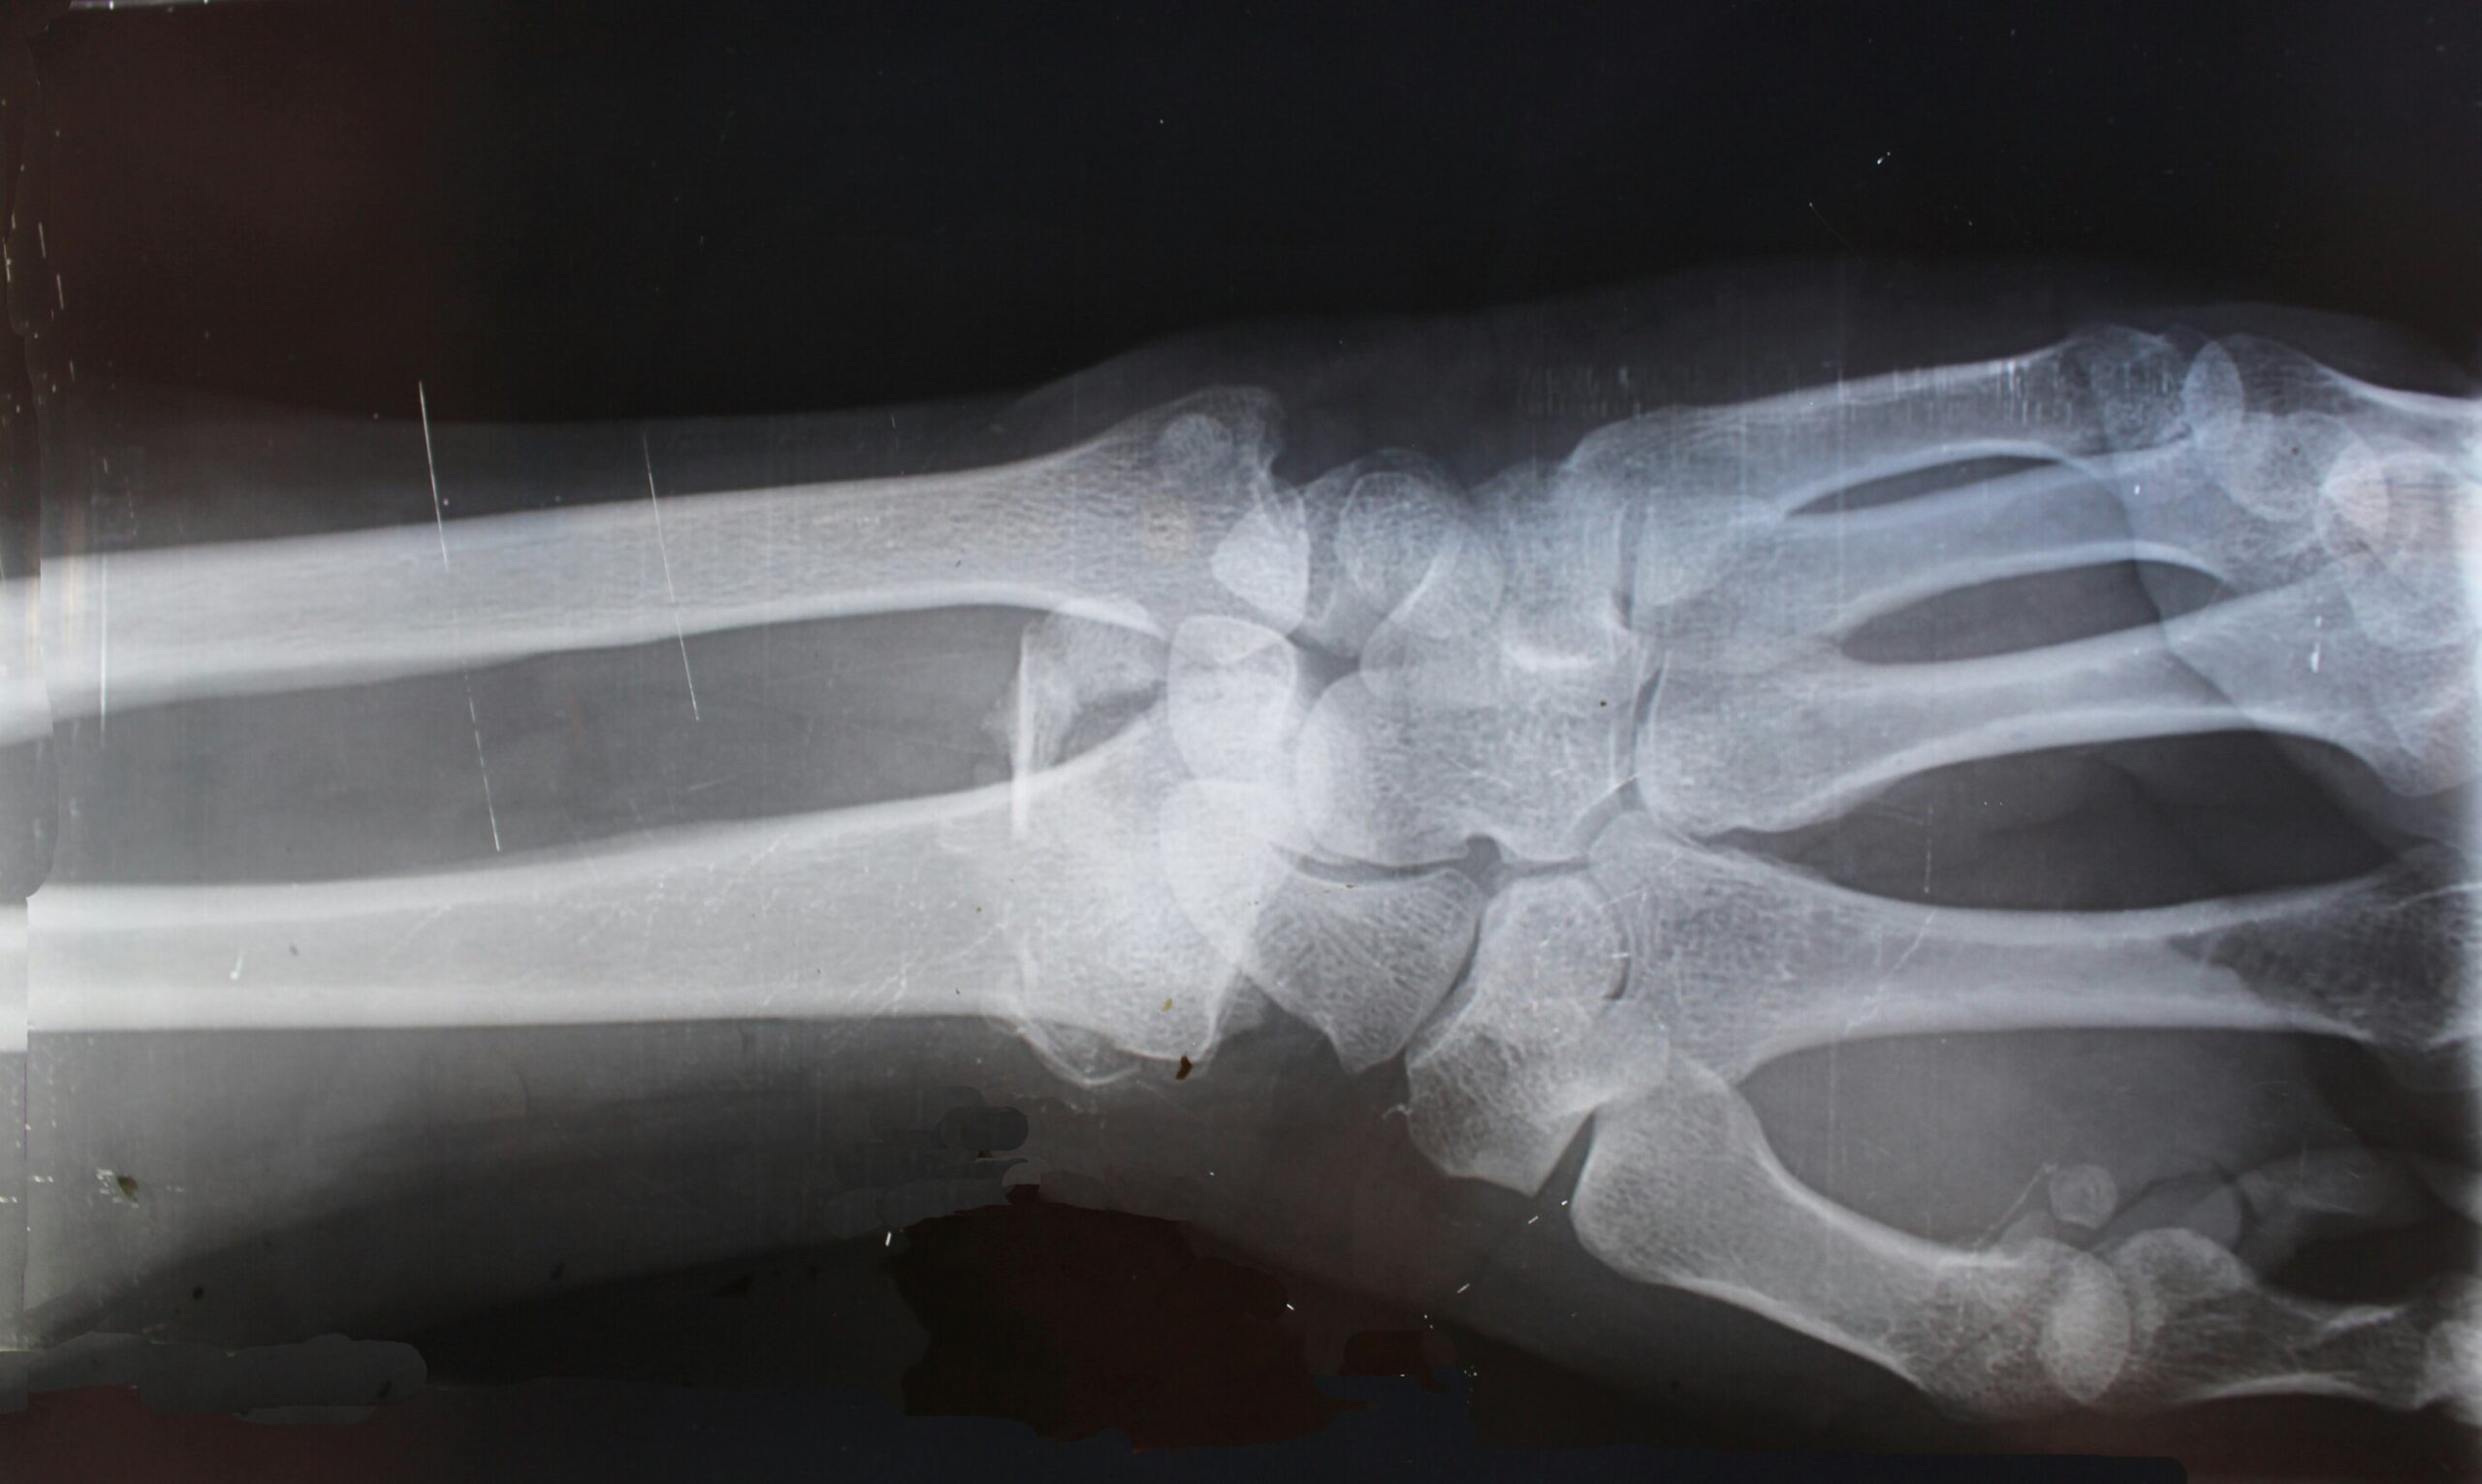

O osteossarcoma é o tipo mais comum de câncer ósseo e geralmente se desenvolve nos braços ou nas pernas. Os sintomas podem incluir dor óssea, caroço ou inchaço e osso que quebra facilmente. Os especialistas estimam que menos de 1.000 pessoas nos EUA desenvolvem osteossarcoma a cada ano. Cerca de 7 em cada 10 pessoas sobrevivem se a doença não se espalhar para outras partes do corpo, mas apenas 2 em cada 10 crianças sobrevivem se a doença se espalhar para fora do local ósseo original.